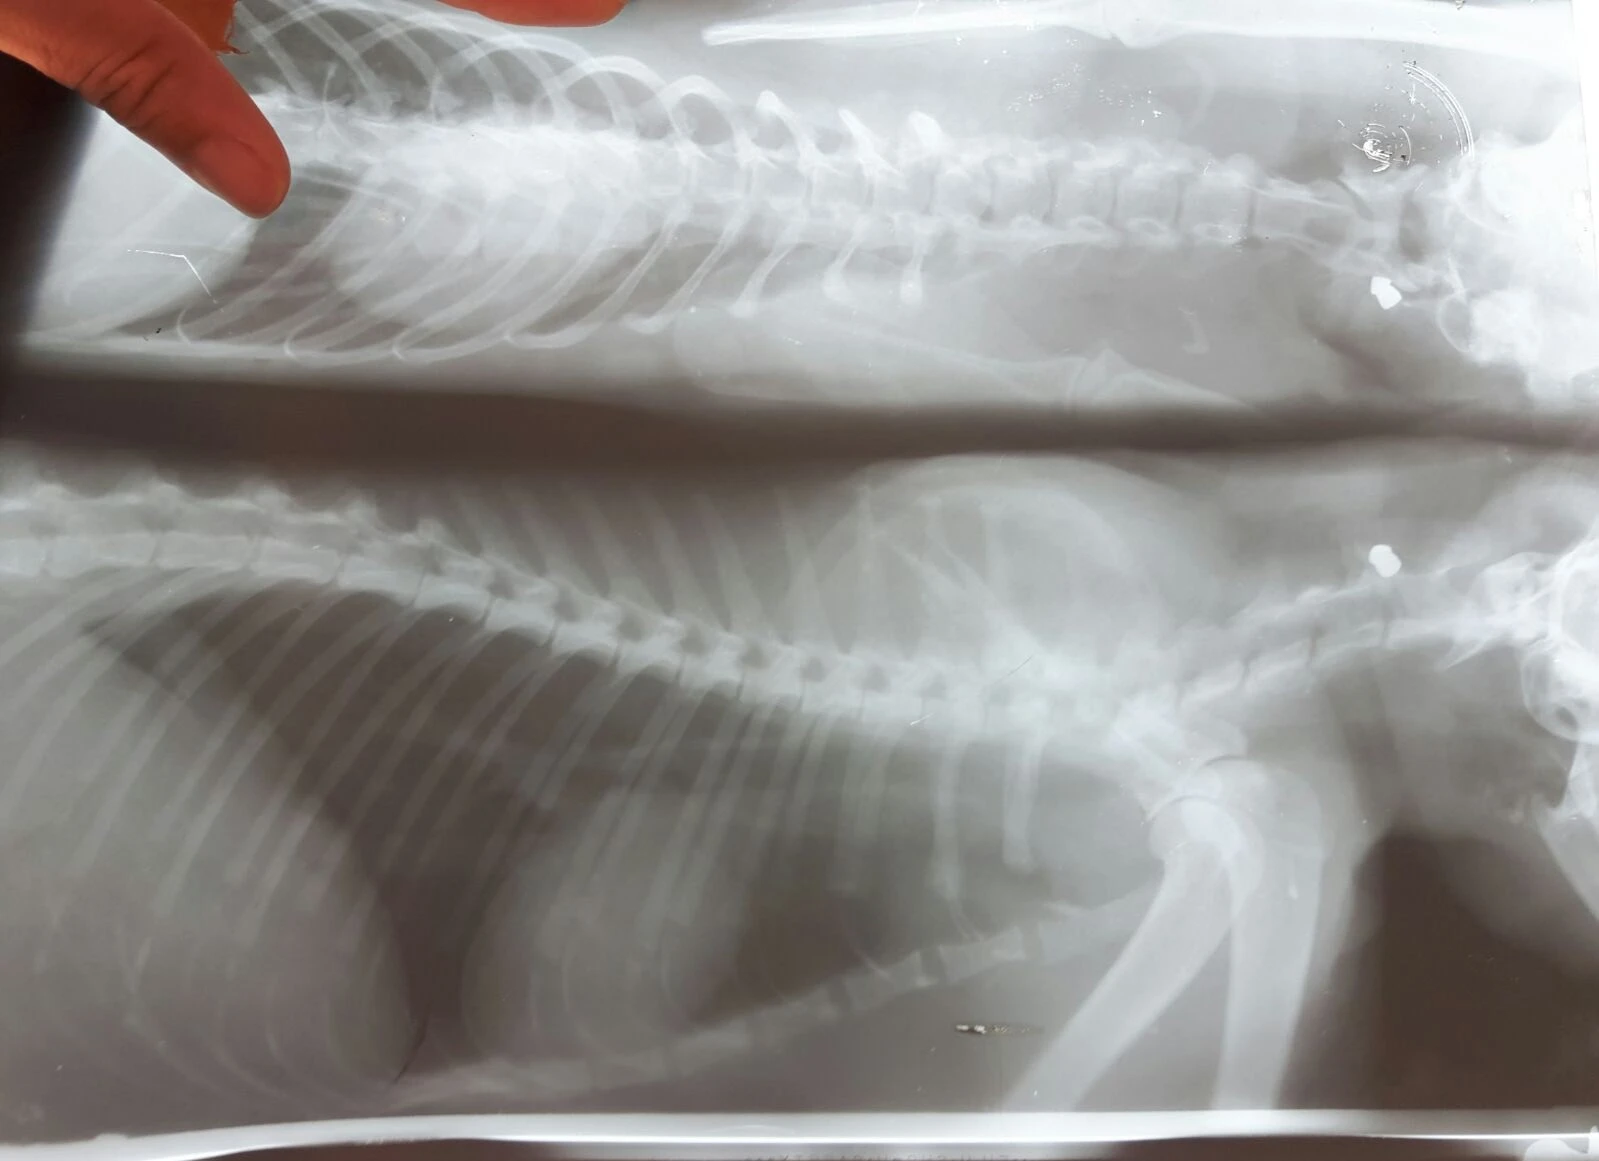

Edinilen bilgiye göre, Konyaaltı ilçesi Hurma Mahallesi 224 Sokak'ta dün gece bir kedi, kimliği belirlenemeyen kişi ya da kişilerce havalı tüfekle ateş edilmesi sonucu yaralandı. Sabah besleme noktasına gelen hayvanseverler bir kedinin hareketsiz şekilde yattığını görünce Büyükşehir Belediyesi Hayvan Bakımevine götürdü. Kedinin, boyun kısmına bir saçma isabet ettiği belirlendi.

Kedilere yüksek bir yerden havalı tüfekle ateş edildiğini dile getiren Gürsel, "Diğer olaylarda polis merkezine şikayete gittik. Ama ateşli silah olmadığı için balistik incelemesi yapılamadı. Bu kedimizin röntgeninde boynunda bir saçma tespit edildi. Şuan tedavisine devam ediliyor. Tekrar polis merkezine ve savcılığa şikayette bulunacağız. Bu şüpheliyi yakalamadıkça olayların arkası kesilmeyecek. Saçmalardan birisi o bölgede oynayan insanlara da gelebilir. Bir canımızın daha saçmaların hedefi olmaması için konunun sonuna kadar takipçisi olacağız" dedi.